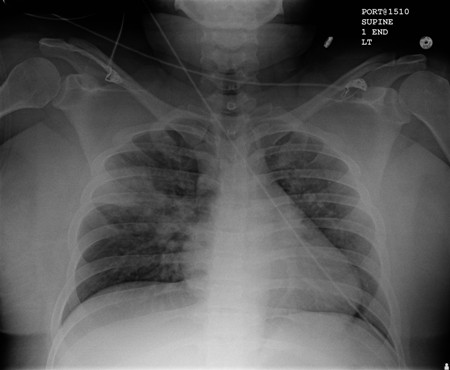

Pneumonia por aspiração

Opacificações precoces mal definidas no lobo superior direito, acima da fissura menor, compatíveis com alterações precoces de pneumonia por aspiração